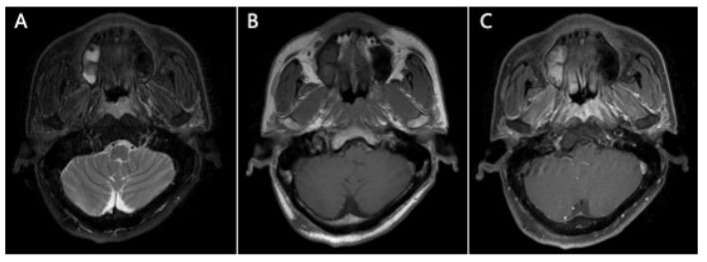

A 53-year old male was hospitalized in our department in August 2021. He had experienced nasal congestion for six months, and the symptom was progressively exacerbated. Magnetic resonance imaging (MRI) showed a mass in the nasopharynx involving bilateral staphylinus externus and petrostaphylinus (Figure 1), accompanied with slightly enlarged bilateral level IIA lymph nodes in the neck. 18F-fluorodeoxy-glucose (18FDP)-PET/CT showed mildly increased glucose metabolism of both the primary mass and cervical nodes. Laboratory tests showed EBV DNA copies of 769 (higher than the normal value of 400 in our hospital) in peripheral blood. Nasopharyngoscopy showed an eminence lesion in the nasopharynx, while tumor cells were not found in the biopsy specimen. Repeated nasopharyngeal biopsies were conducted for two more times while histopathological examination only showed acute and chronic inflammation of the squamous epithelium with few variant cells, hyperplasia of lymphatic tissue and minute vessels in submucosa. The diagnosis could not be pathological confirmed while the patient was highly suspected of NPC with the symptom of nasal congestion, the radiological manifestations and elevated EBV DNA copies. Furthermore, he was from Sihui city where the incidence of NPC reached 20.91/100,000 [1].

Figure 1: MRI scan showed an apparent contrast-enhancing soft tissue lesion in the nasopharynx involving bilateral staphylinus externus and petrostaphylinus (A) T2-weighted image of the lesion (B) T1-weighted image (C) contrast-enhanced T1-weighted image.